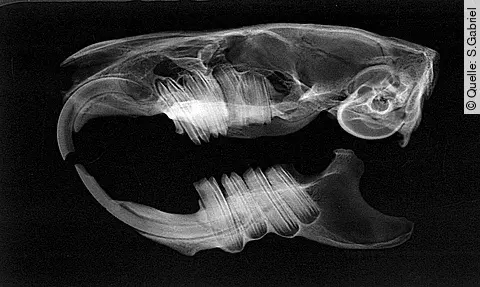

Röntgenbild

Quelle: S.Gabriel

Diagnostik und TherapieMolarenextraktion bei Heimtieren

Veränderungen an den Backenzähnen und deren Folgeerkrankungen haben in der Heimtierpraxis eine große Bedeutung. Die elodonten Backenzähne bei Kaninchen und Nagern stellen wegen ihrer besonderen Anatomie eine große Herausforderung an die Extraktionstechnik dar. Lesen Sie im Artikel über Diagnostik und Therapie.